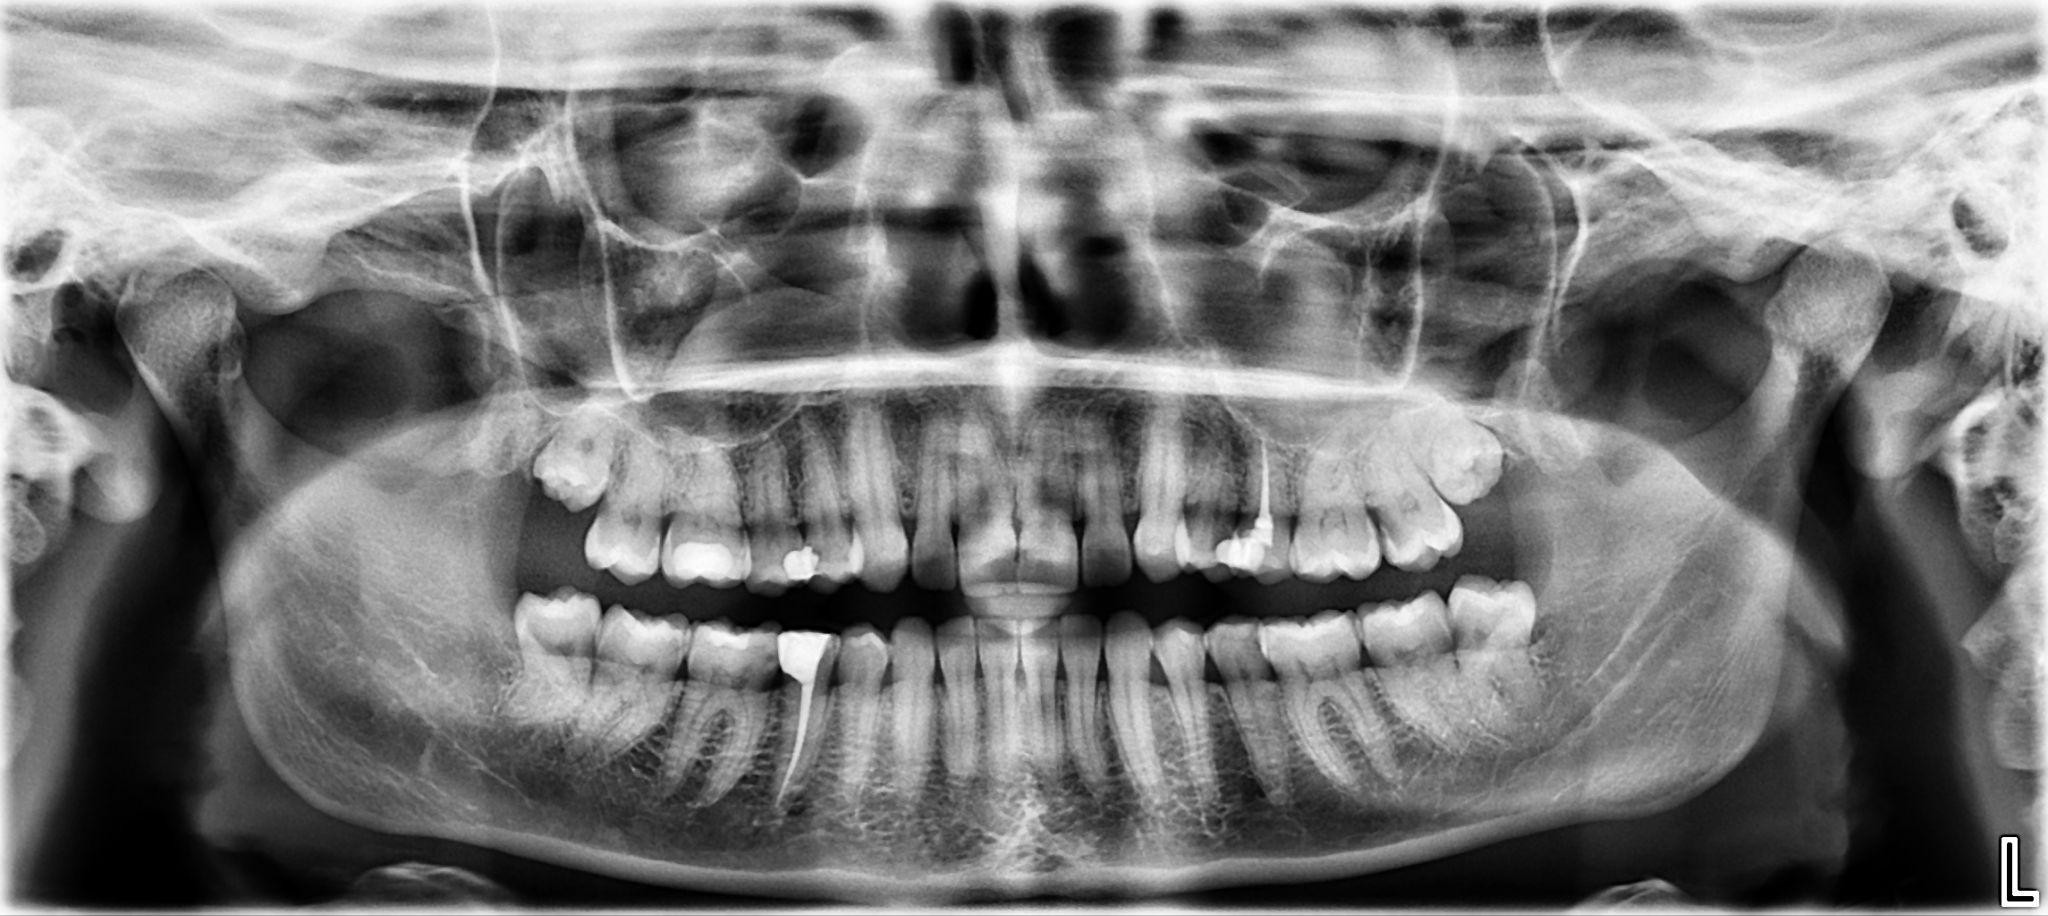

1. What options can be selected for the first quadrant of this panoramic X ray?

2. What options can be selected for the second quadrant of this panoramic X ray?

3. What options can be selected for the third quadrant of this panoramic X ray?

4. What options can be selected for the forth quadrant of this panoramic X ray?